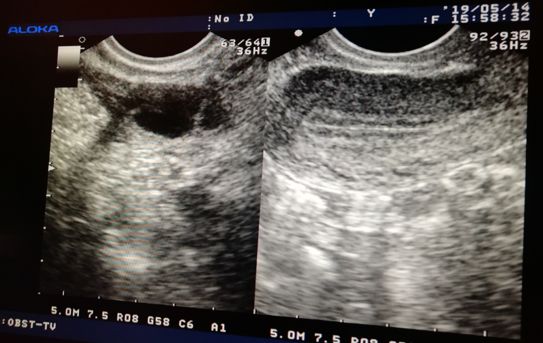

超声监测法是准确可靠的,它最能客观反映卵泡生长发育状况,观察是否有排卵,并同步反映子宫内膜的发育状况。

而且 阴道超声相对于腹部超声监测排卵更好,因为阴道超声探头更接近子宫和卵巢,分辨率高,更准确。